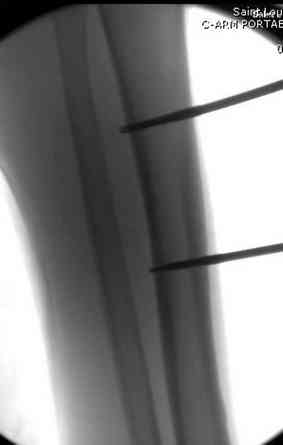

здесь случай с политравмой, перелом зафиксирован наружным фиксатором, после третьей irrigation&debridment фиксация бедра пластиной с последующей кожной пластикой.